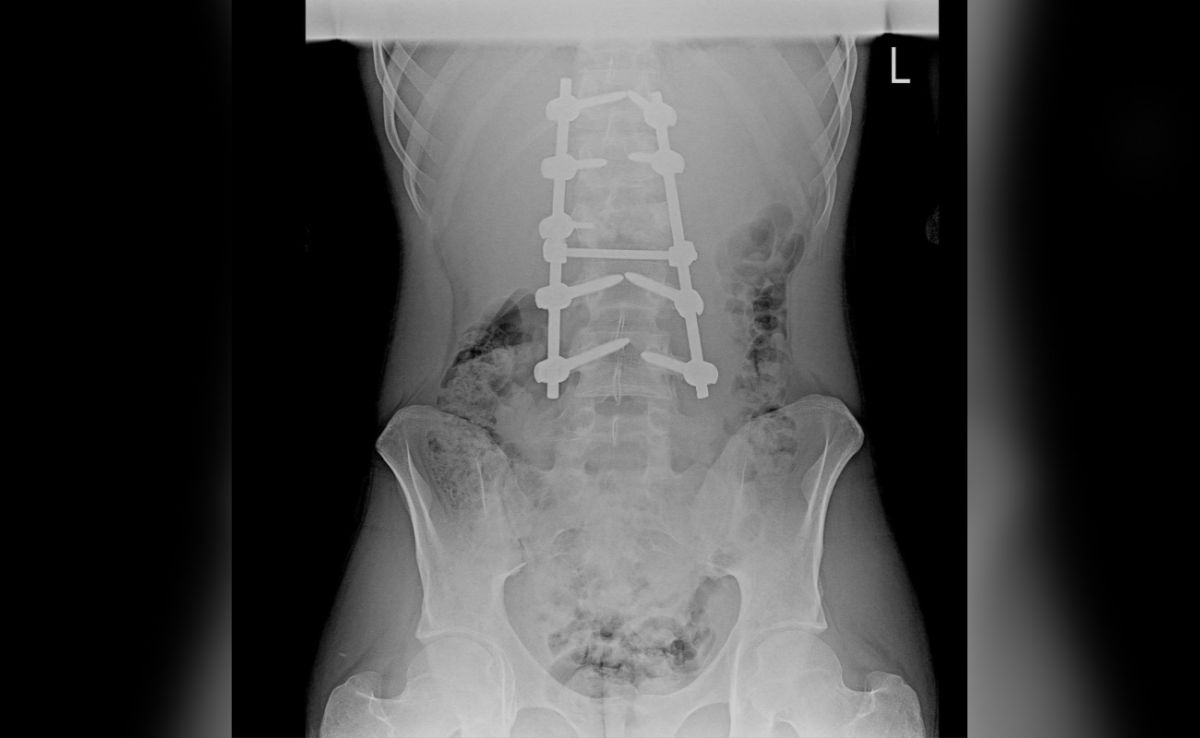

В областной больнице №1 врачи успешно провели сложнейшую операцию по извлечению осколка пули, который застрял в непосредственной близости от спинного мозга молодого мужчины. По словам медиков, ранение было крайне опасным, так как любое смещение инородного тела могло привести к необратимой парализации.

Как сообщает Минздрав региона, осколок, пробив легкое, достиг области позвоночника и застрял среди нервных волокон. Хирургам удалось извлечь его, не повредив нервные ткани и избежав кровотечения. Уникальность операции заключалась в использовании специального магнита для фиксации металлического опасного инородного тела, что позволило контролировать его положение в момент вскрытия оболочек спинного мозга.